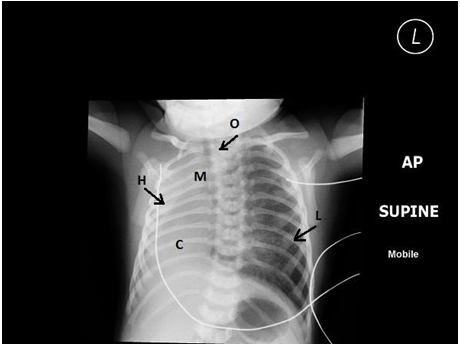

The second was a baby girl, full term normal vaginal delivery, weighing 2 KG. The baby showed all symptoms and signs of esophageal atresia with tracheoesophageal fistula. The pre op X rays showed an NGT coiled in the upper pouch and plenty of air in the GI tract indicating presence of a fistula. The Rt lung was normal and large and the left hemithorax was occupied by the heart. No lung tissue could be identified on plain films.

AUL, Absent Lt Upper Lobe; LLB,  Lt. Lower Lobe Bronchus;   ALL, Aberrant artery from the aortic arch supplying Lt. Lower Lobe;  L, hyperinflation of contralateral lung; LLL, Lt. Lower Lobe.

With a suspicion of Lt lung agenesis, a high resolution contrast enhanced CT scan was ordered. This showed agenesis of the Lt upper lobe, a rudimentary Lt lower lobe and an aberrant artery from the aortic arch supplying the left lower lobe. This was consistent with a Type 3 of lobar agenesis, and hypoplastic, ipsilateral pulmonary artery with normal bronchus of the lower lobe. An aberrant systemic arterial supply to lower lobe was an additional finding.